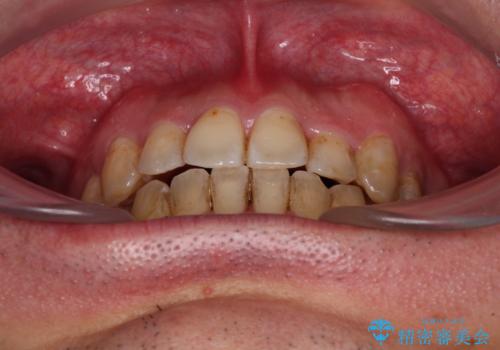

- 虫歯が多く、セラミッククラウンにより虫歯治療を行っている途中で矯正治療をしたいとのことで来院された患者様です。

上顎前歯が舌側に転位しており、なるべく早く楽に矯正したいとのことで、ワイヤー矯正を行うこととしました。

虫歯治療途中の歯は仮歯が装着されていたため、そのまま矯正治療を行い、矯正後に補綴治療を行うこととしました。